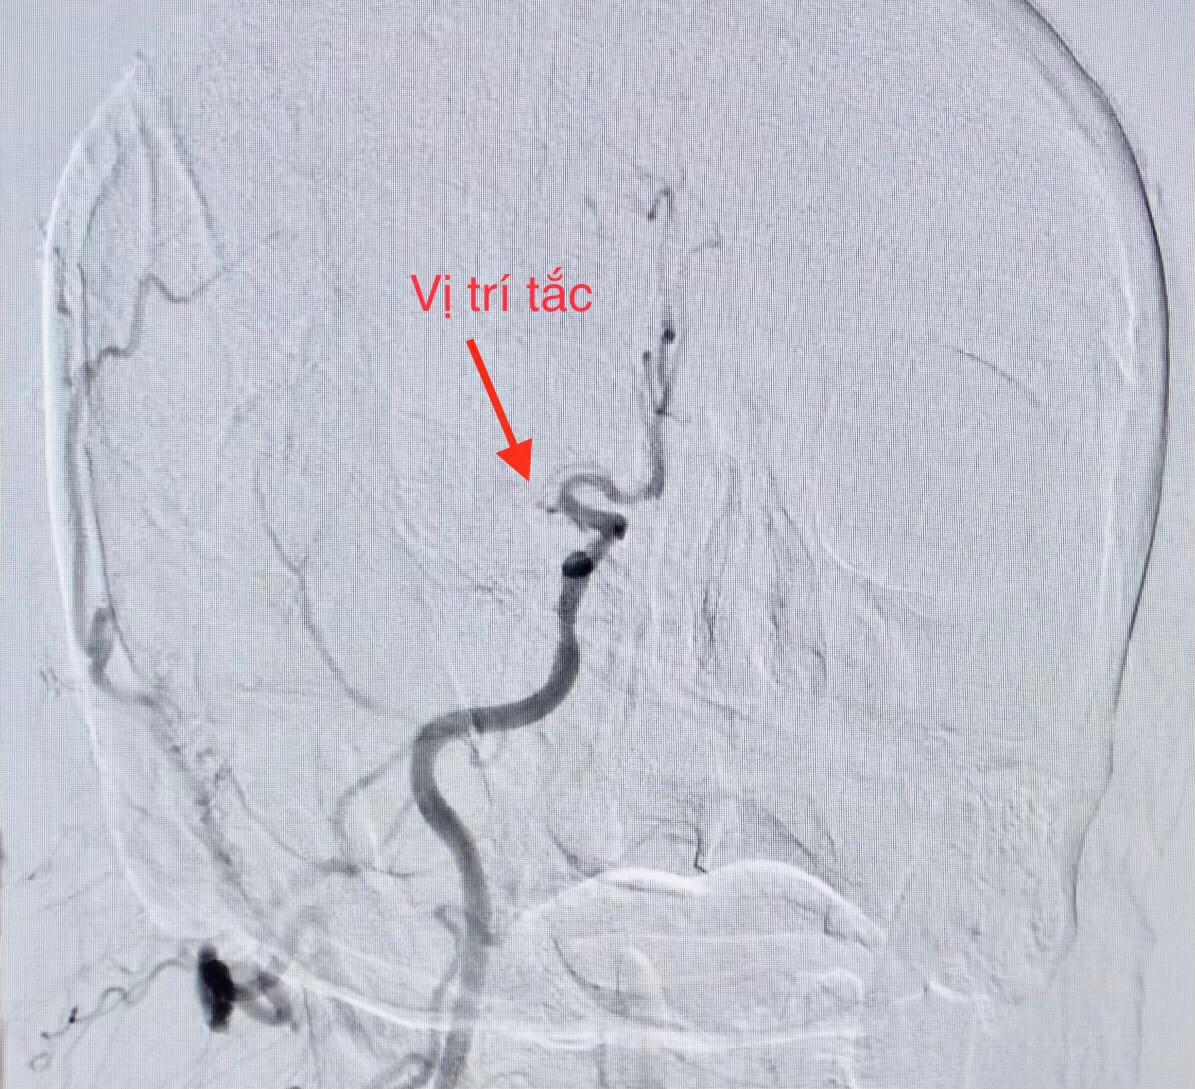

Thời điểm chuẩn bị đặt ống thông để can thiệp mạch vành, bệnh nhân liệt nửa người bên trái và nói đớ. Nhận định đây là một trường hợp hiếm gặp phối hợp giữa nhồi máu cơ tim cấp (do tắc động mạch vành) và nhồi máu não cấp (do tắc một mạch máu ở não), ê-kíp can thiệp mạch máu não lập tức được báo động để cùng phối hợp điều trị cho bệnh nhân. Kết quả CTscan não đúng như chẩn đoán.

Ê-kíp can thiệp tim mạch trong thời gian khoảng 40 phút đã hoàn tất nong động mạch vành bị tắc và tiến hành đặt giá đỡ (stent), giúp tái lập dòng máu nuôi tim. Ngay sau đó ê-kíp can thiệp mạch não chụp kiểm tra phát hiện tắc động mạch não giữa bên phải; thủ thuật lấy huyết khối tái thông mạch máu bị tắc với thời gian 20 phút.

Hình DSA mạch não trước can thiệp |